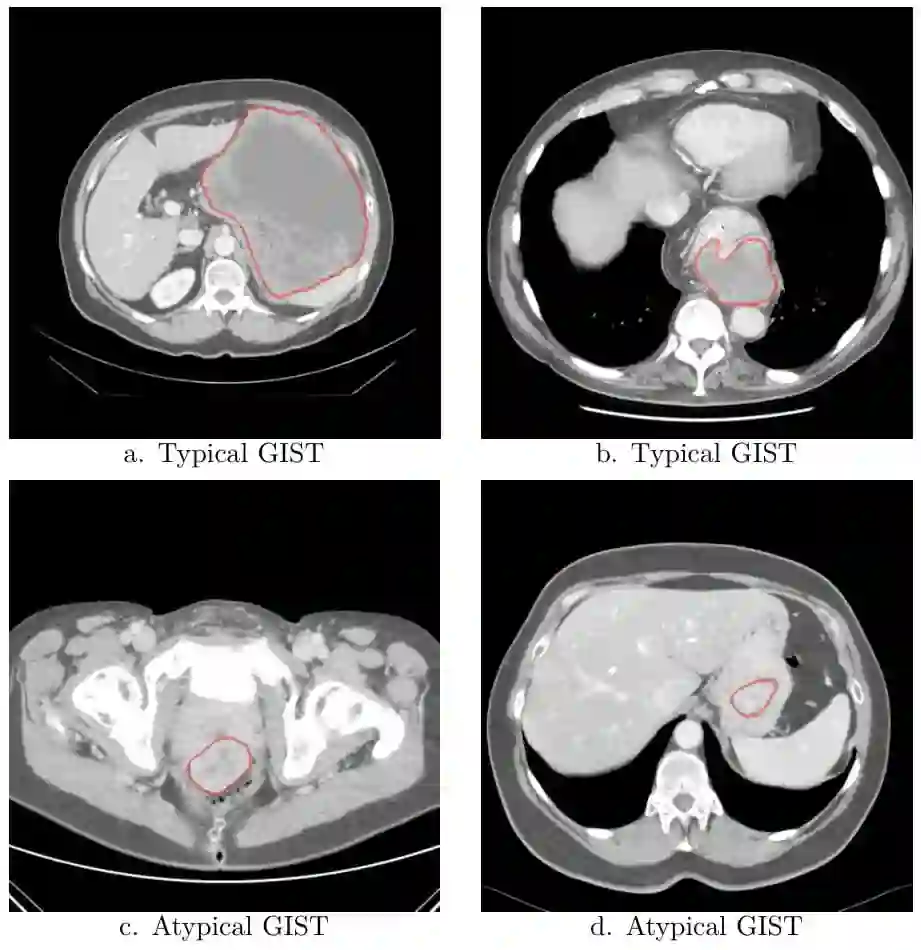

Distinguishing gastrointestinal stromal tumors (GISTs) from other intra-abdominal tumors and GISTs molecular analysis is necessary for treatment planning, but challenging due to its rarity. The aim of this study was to evaluate radiomics for distinguishing GISTs from other intra-abdominal tumors, and in GISTs, predict the c-KIT, PDGFRA,BRAF mutational status and mitotic index (MI). All 247 included patients (125 GISTS, 122 non-GISTs) underwent a contrast-enhanced venous phase CT. The GIST vs. non-GIST radiomics model, including imaging, age, sex and location, had a mean area under the curve (AUC) of 0.82. Three radiologists had an AUC of 0.69, 0.76, and 0.84, respectively. The radiomics model had an AUC of 0.52 for c-KIT, 0.56 for c-KIT exon 11, and 0.52 for the MI. Hence, our radiomics model was able to distinguish GIST from non-GISTS with a performance similar to three radiologists, but was not able to predict the c-KIT mutation or MI.